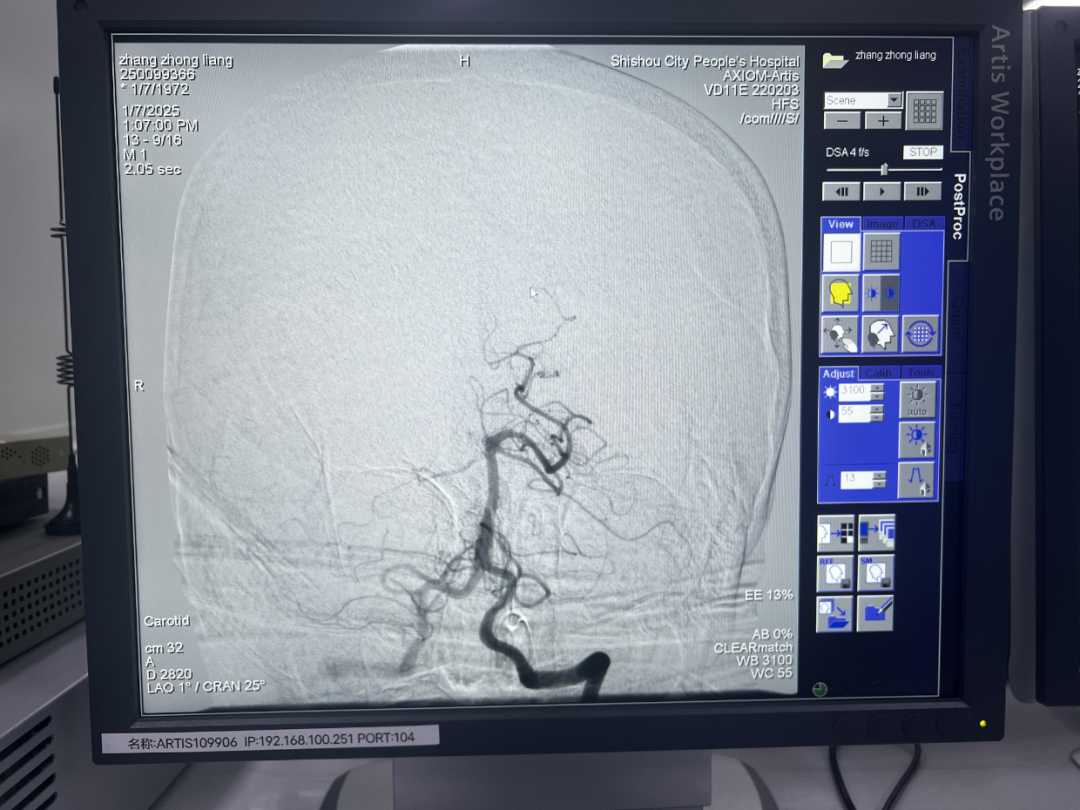

2025年1月6日17时34分,53岁的患者张某某因头晕伴右侧肢体无力7.5小时由调关镇卫生院紧急送往石首市人民医院救治。患者称上午10时左右在活动中突感头晕、右侧肢体无力且持续未缓解。 张某某入院时,生命体征虽平稳,但神经系统已有明显症状。神经内科医师朱立平经过细心诊察,初步诊断为“脑梗塞”,并制定详细的治疗方案。次日上午9:20分,患者病情突变。护士王萍巡视发现患者神志为嗜睡状、表情淡漠、左侧肢体全瘫,头颈部CTA检查后,考虑为血栓脱落。神经内科团队迅速组织讨论与会诊,介入室随即投入战斗。 由神经内科主任张伟、医师朱立平、介入专科护士汪杨组成的团队紧密协作,通过脑血管造影,明确了患者“右侧大脑后动脉闭塞”这一关键病因。时间就是生命。面对发病23小时后仍在不断衍变的进展性脑卒中,神经内科团队在荆州市中心医院神经内科专家陈立教授的指导下,成功抽吸,取出血栓,术后造影显示:“基底动脉及双侧大脑后动脉恢复通畅”。 手术结束后,张某某安返病房。在医护人员的精心治疗护理下,张某某神志转清,病情稳定,双侧肢体肌力恢复,精神状态显著改善。 此次颅内动脉取栓术的成功,彰显了市人民医院神经内科的精湛技术和团队精神。神经内科将秉持初心,砥砺前行,不断钻研新技术,开展新业务,为全市脑血管疾病患者保驾护航。